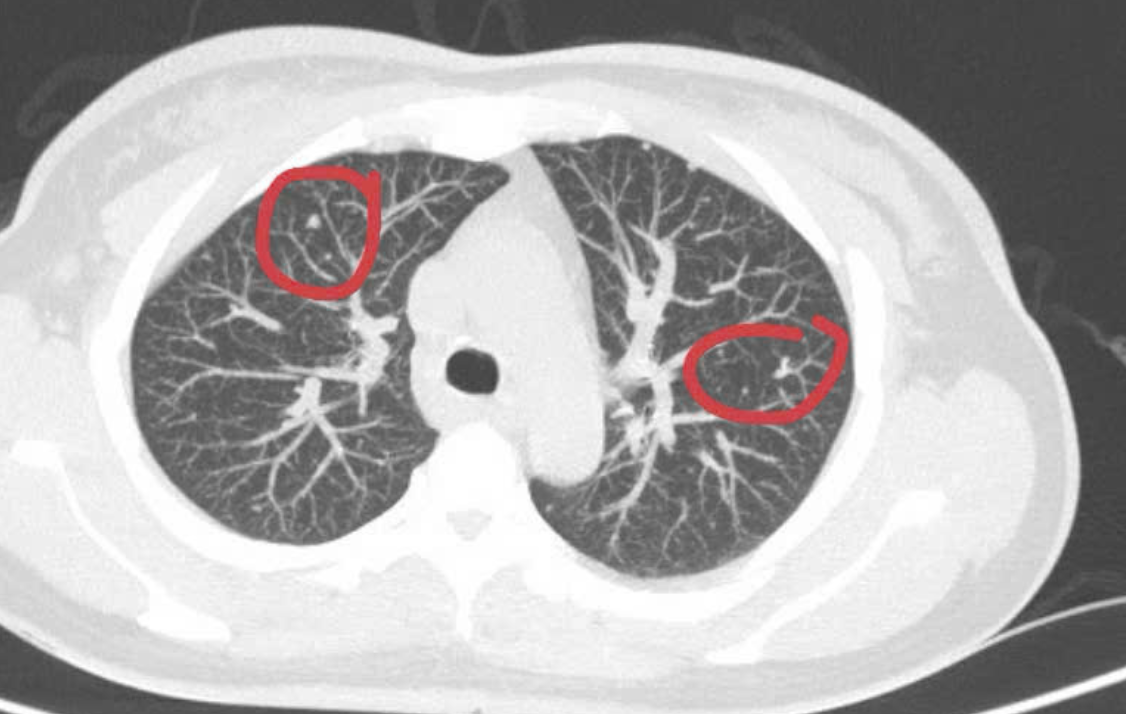

Theo bác sĩ Duy Anh, kết quả khám lâm sàng và chụp CT-scan toàn thân của bệnh nhân phát hiện có khối u vú phải kích thước 25x52mm, nhiều hạch to tròn, phổi hai bên có các nốt mờ ở màng phổi.